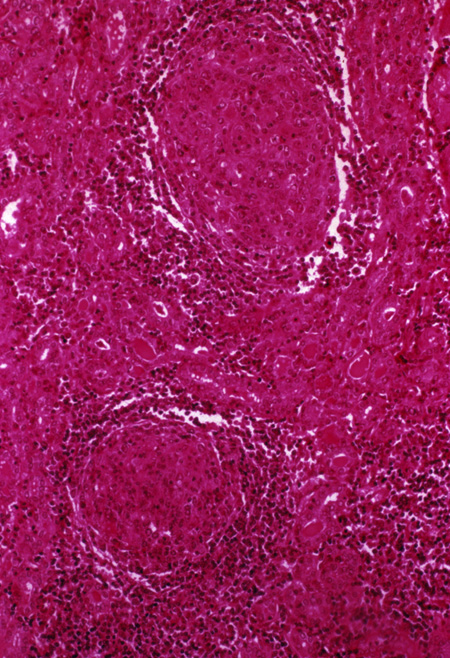

Lymphocytic (Hashimoto's) Thyroiditis

Chronic lymphocytic thyroiditis - Case 20 - YouTube

Chronic lymphocytic thyroiditis - case 20 Tamas Solymosi. Subscribe Subscribed Unsubscribe 20 20. Loading Loading Working Add to. Want to watch this again later? Sign in to add this video to a playlist. Sign in. Share More. ... View Video

Chronic lymphocytic thyroiditis - Case 15 And Other Edifying ...

Chronic lymphocytic thyroiditis - case 15 and Other edifying cases - case 12 Tamas Solymosi. Subscribe Subscribed Unsubscribe 20 20. Addressing Hashimoto’s Thyroiditis with Dr. Izabella Wentz - Dr. Trevor Cates - Duration: 33:29. by Trevor Cates 16,160 views. ... View Video